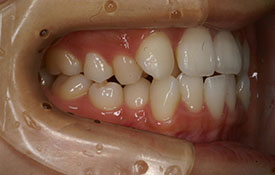

| プロフィール | 42歳 女性 |

| 所見 | 他院で行われた矯正歯科治療後の後戻りに悩まれて来院されました。 アイライナーの装着は、1日平均20時間ほどでした。 |